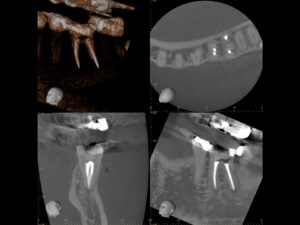

初診時CT。根管治療を何度も繰り返し行ったことで、歯根は無駄に削られて歯質が薄くなり、歯根の先端には穿孔(パーフォレーション)を生じていた。根尖病巣は認めない。